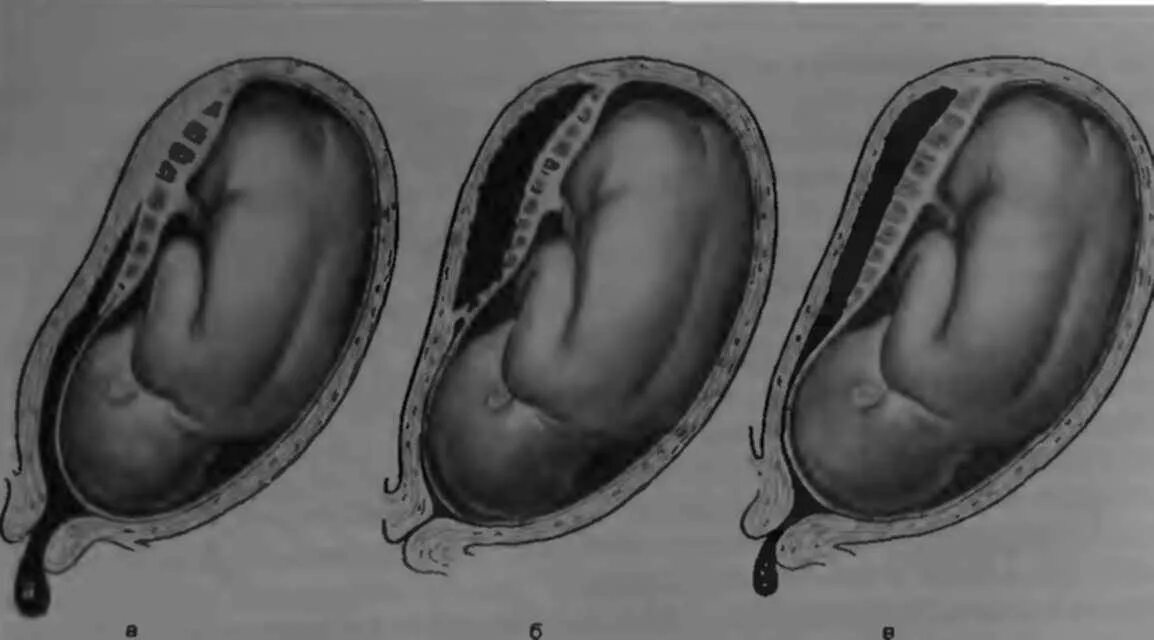

Плацента на 6 неделе беременности